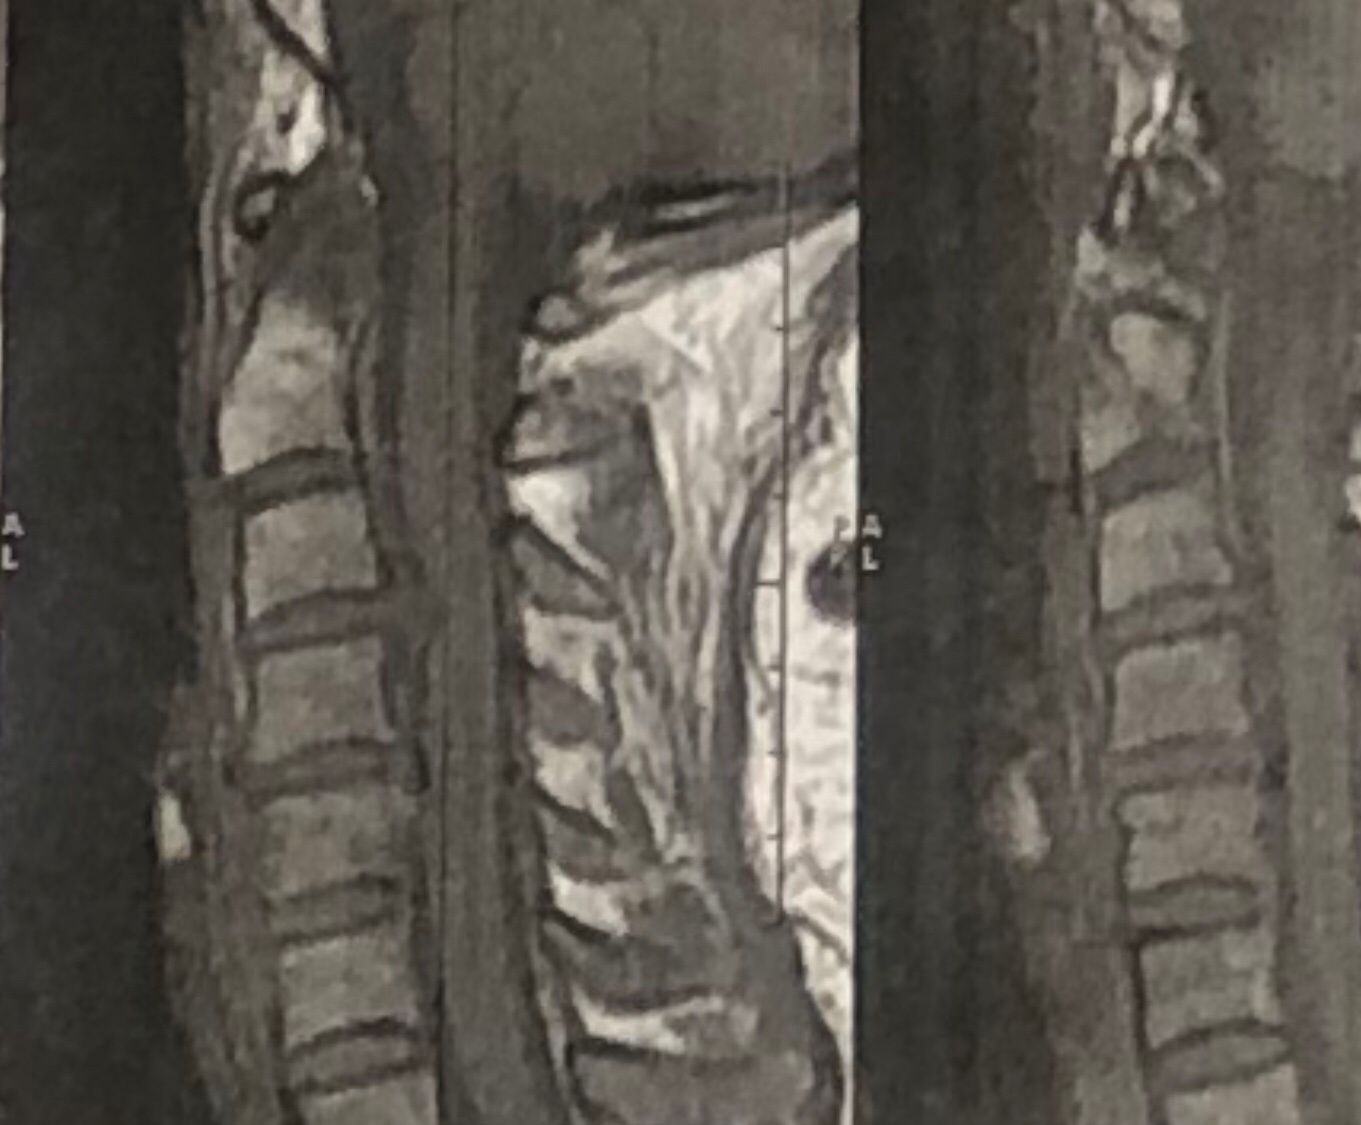

41 years old man presented to my clinic in October 2023 with acute and sever R neck pain with radicular pain to his R upper extremity along C6 dematom since 2 weeks ago. Examination didn’t show any upper motor signs. Was suggested urgent surgery

I ordered EMG/ NCV : showed mild R C6, C7 irritation without any active axonal loss

In his MRI was reported R. para R. IVF Massive extrusion. I decided to control his pain and manage this patient with reevaluation of patient every other session. For 5 sessions i just used acupuncture and laser and IFC and mild adjustments to his R. T3-T7 and mild arthosteem to above and below involved segment. Cervical adjustment considered contraindicated for this patient. From session 6th- 8th i started to use mild/gentle cervical decompression. He used soft cervical collar all the time. His pain decreased by 80 percent

I gave him cervical traction pump to be used 3-5 times per day at home for the next 3 months and i released the patient. He was evaluated every week once for one month and after that every 2 weeks. After 3 month I repeated MRI. Size of the herniated disc was reduced greater than 50 percent. Asked him to do another mri in 6 months

MRIs before and after proper management of this patient: